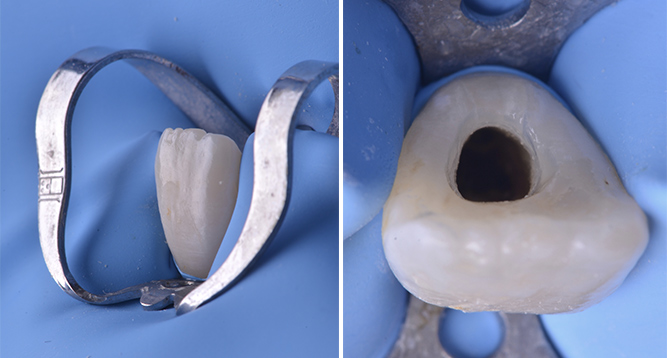

Après mise en place du champ opératoire la cavité d’accès est réalisée. Cette dernière de taille légèrement plus importante qu’une cavité standard doit s’adapter à la situation clinique et à la nécessité de pouvoir réaliser avec précision le bouchon apical.

Fig. 03 et 04 : isolation unitaire à l’aide d’un crampon incisif et vue clinique de la cavité d’accès.